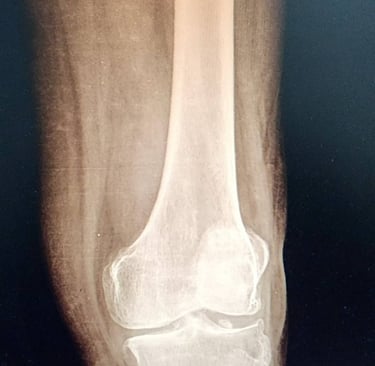

En muchos casos, es necesario recurrir a estudios de imagen para obtener una visión más clara del estado de la articulación. Existen diversas pruebas que permiten identificar muchos tipos de lesion como: fracturas, lesiones de ligamentos, lesión del cartílago, meniscopatias o lesiones de los meniscos, inflamacion, derrame articular . Asimismo, en ciertas situaciones, los estudios de laboratorio pueden ayudar a detectar enfermedades inflamatorias o afecciones de la rodilla.